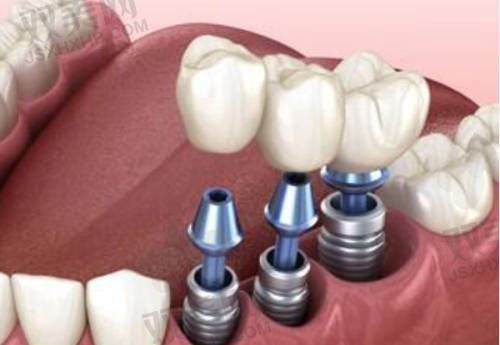

种植体植入手术

在局部麻醉下,医生会在患者的牙槽骨上制备一个合适的种植窝,然后将种植体植入其中。手术过程中,医生会严格遵循无菌操作原则,确保手术的安心性。植入种植体后,患者需要等待一段时间,让种植体与牙槽骨形成骨结合,这个过程一般需要3 - 6个月。

安装基台和牙冠

当种植体与牙槽骨达到良好的结合后,患者需要再次回到医院,进行基台的安装。基台是连接种植体和牙冠的部件,它的安装需要严谨的操作。安装基台后,医生会取牙齿模型,制作与患者口腔情况和邻牙相匹配的牙冠。末尾,将牙冠安装在基台上,完成一颗种植牙的治疗。